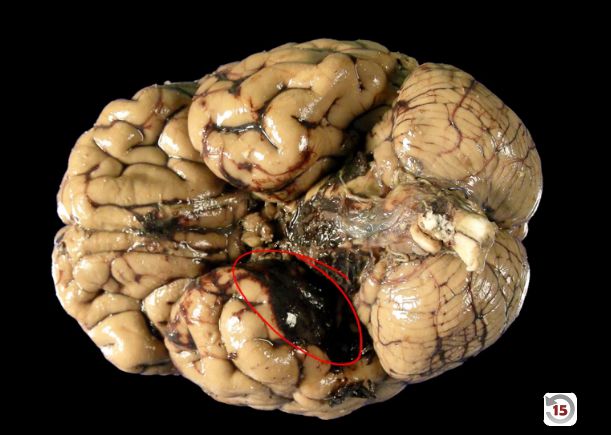

The image showing a bleed over the arachnoid layer but under the dura is suggestive of a _____ hemorrhage.